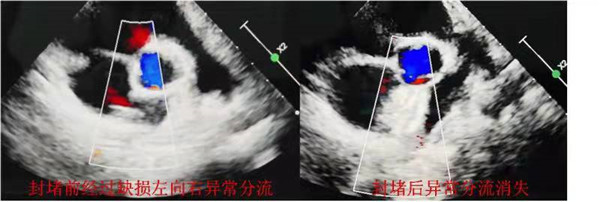

周四早晨八点,小雯准时被送进大明宫院区导管室。麻醉科代志明医生顺利完成插管全醉。在裴斐主任的亲自指挥下,导管室王荣等护士配合下,由相里伟医生主刀,熟练穿刺股静脉,留置鞘建立通路。在超声科金鑫医生的超声引导下,将导丝和封堵器输送系统安全顺利的沿股静脉、下腔静脉送入右心房,小心通过房间隔缺损处,建立手术通道。根据术前金鑫医生的精确测量缺损大小,选用最新一代12mm单铆氧化膜封堵器,通过建立好的手术轨道将体外装配好的房间隔缺损封堵器缓慢送达心腔内准确位置,超声定位下依次打开封堵器的左右侧伞盘,如同术前预判的一样,封堵器完美贴合,房间隔缺损畸形的异常血流瞬间完全消失,心内其他解剖结构未受影响,心电图及生命体征监测平稳正常,完全释放封堵器后撤出输送系统,手术获得成功。整个手术过程不到20分钟,全程经胸超声引导X线0辐射,手术切口3mm,真正达到了微创,绿色和简捷。